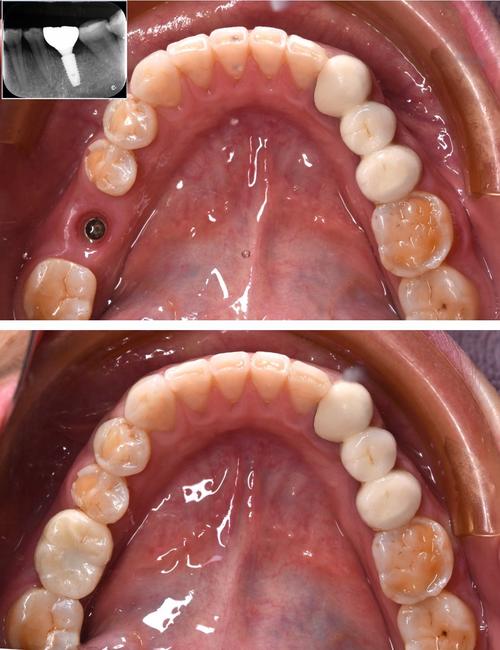

种植牙的核心在于技术是否成熟,而平顶山的口腔医疗机构已普遍引入数字化种植设备,CBCT(锥形束CT)可实现口腔三维精准成像,帮助医生判断牙槽骨的厚度、密度及神经血管位置;3D打印导板技术能辅助手术精准定位种植位置、角度和深度,减少创伤;部分机构还配备了口腔扫描仪,替代传统取模,提升修复体的贴合度,这些技术的应用,使得种植牙的成功率大幅提升,目前平顶山正规机构的种植牙成功率可达95%以上,与国内一线城市水平相当。

- 方案设计:根据检查结果,医生与患者共同确定种植体品牌、位置及修复方式,必要时借助数字化导板规划手术路径。

- 植入种植体:在局部麻醉下,通过微创手术将种植体植入牙槽骨,手术时间约30分钟-1小时/颗。

- 安装基台与牙冠:骨结合后,安装基台并取模,制作牙冠,戴牙后完成修复。